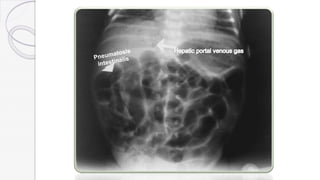

 1. Plain abdominal x-rays :

>Pneumatosis intestinalis (air in the bowel wall) is diagnostic;

>Portal or hepatic venous gas.

>Bowel wall edema.

>Pneumoperitoneum indicates a perforation.

>Appearance of a mass.